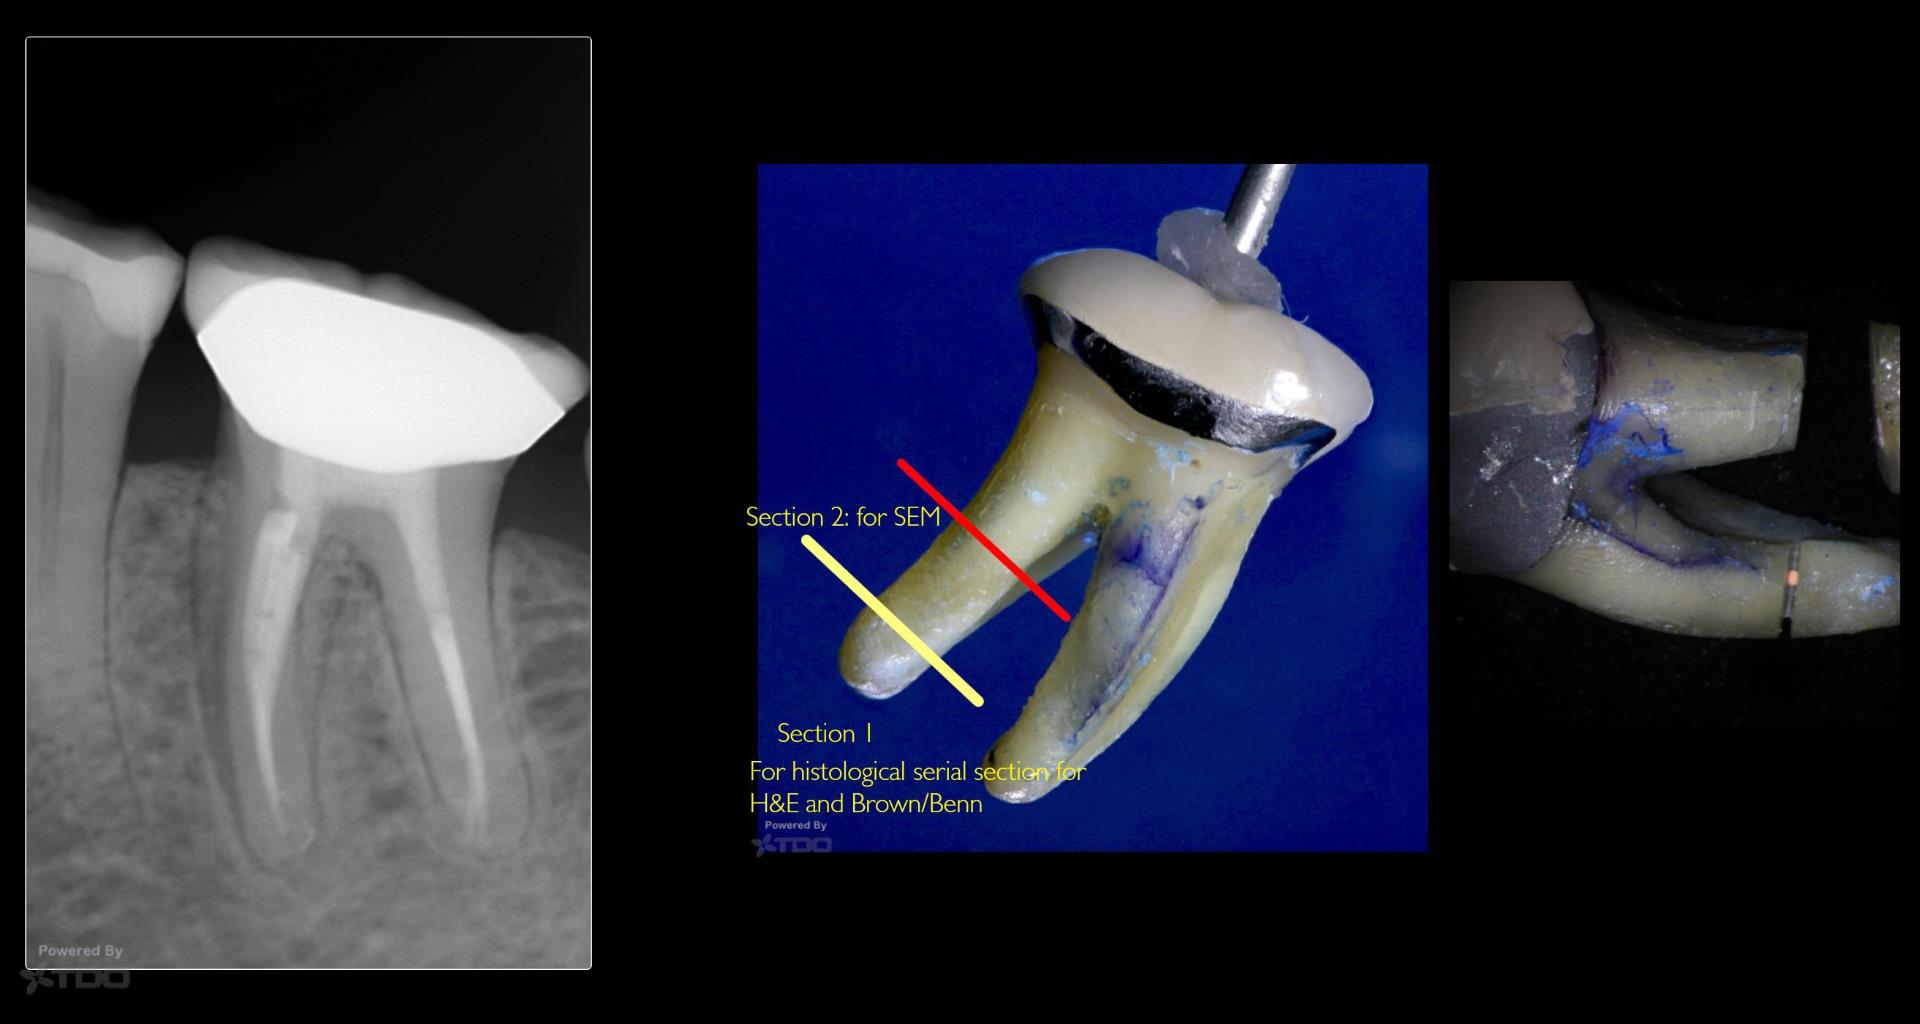

The “Good” root

Gary Carr

February 27, 2019